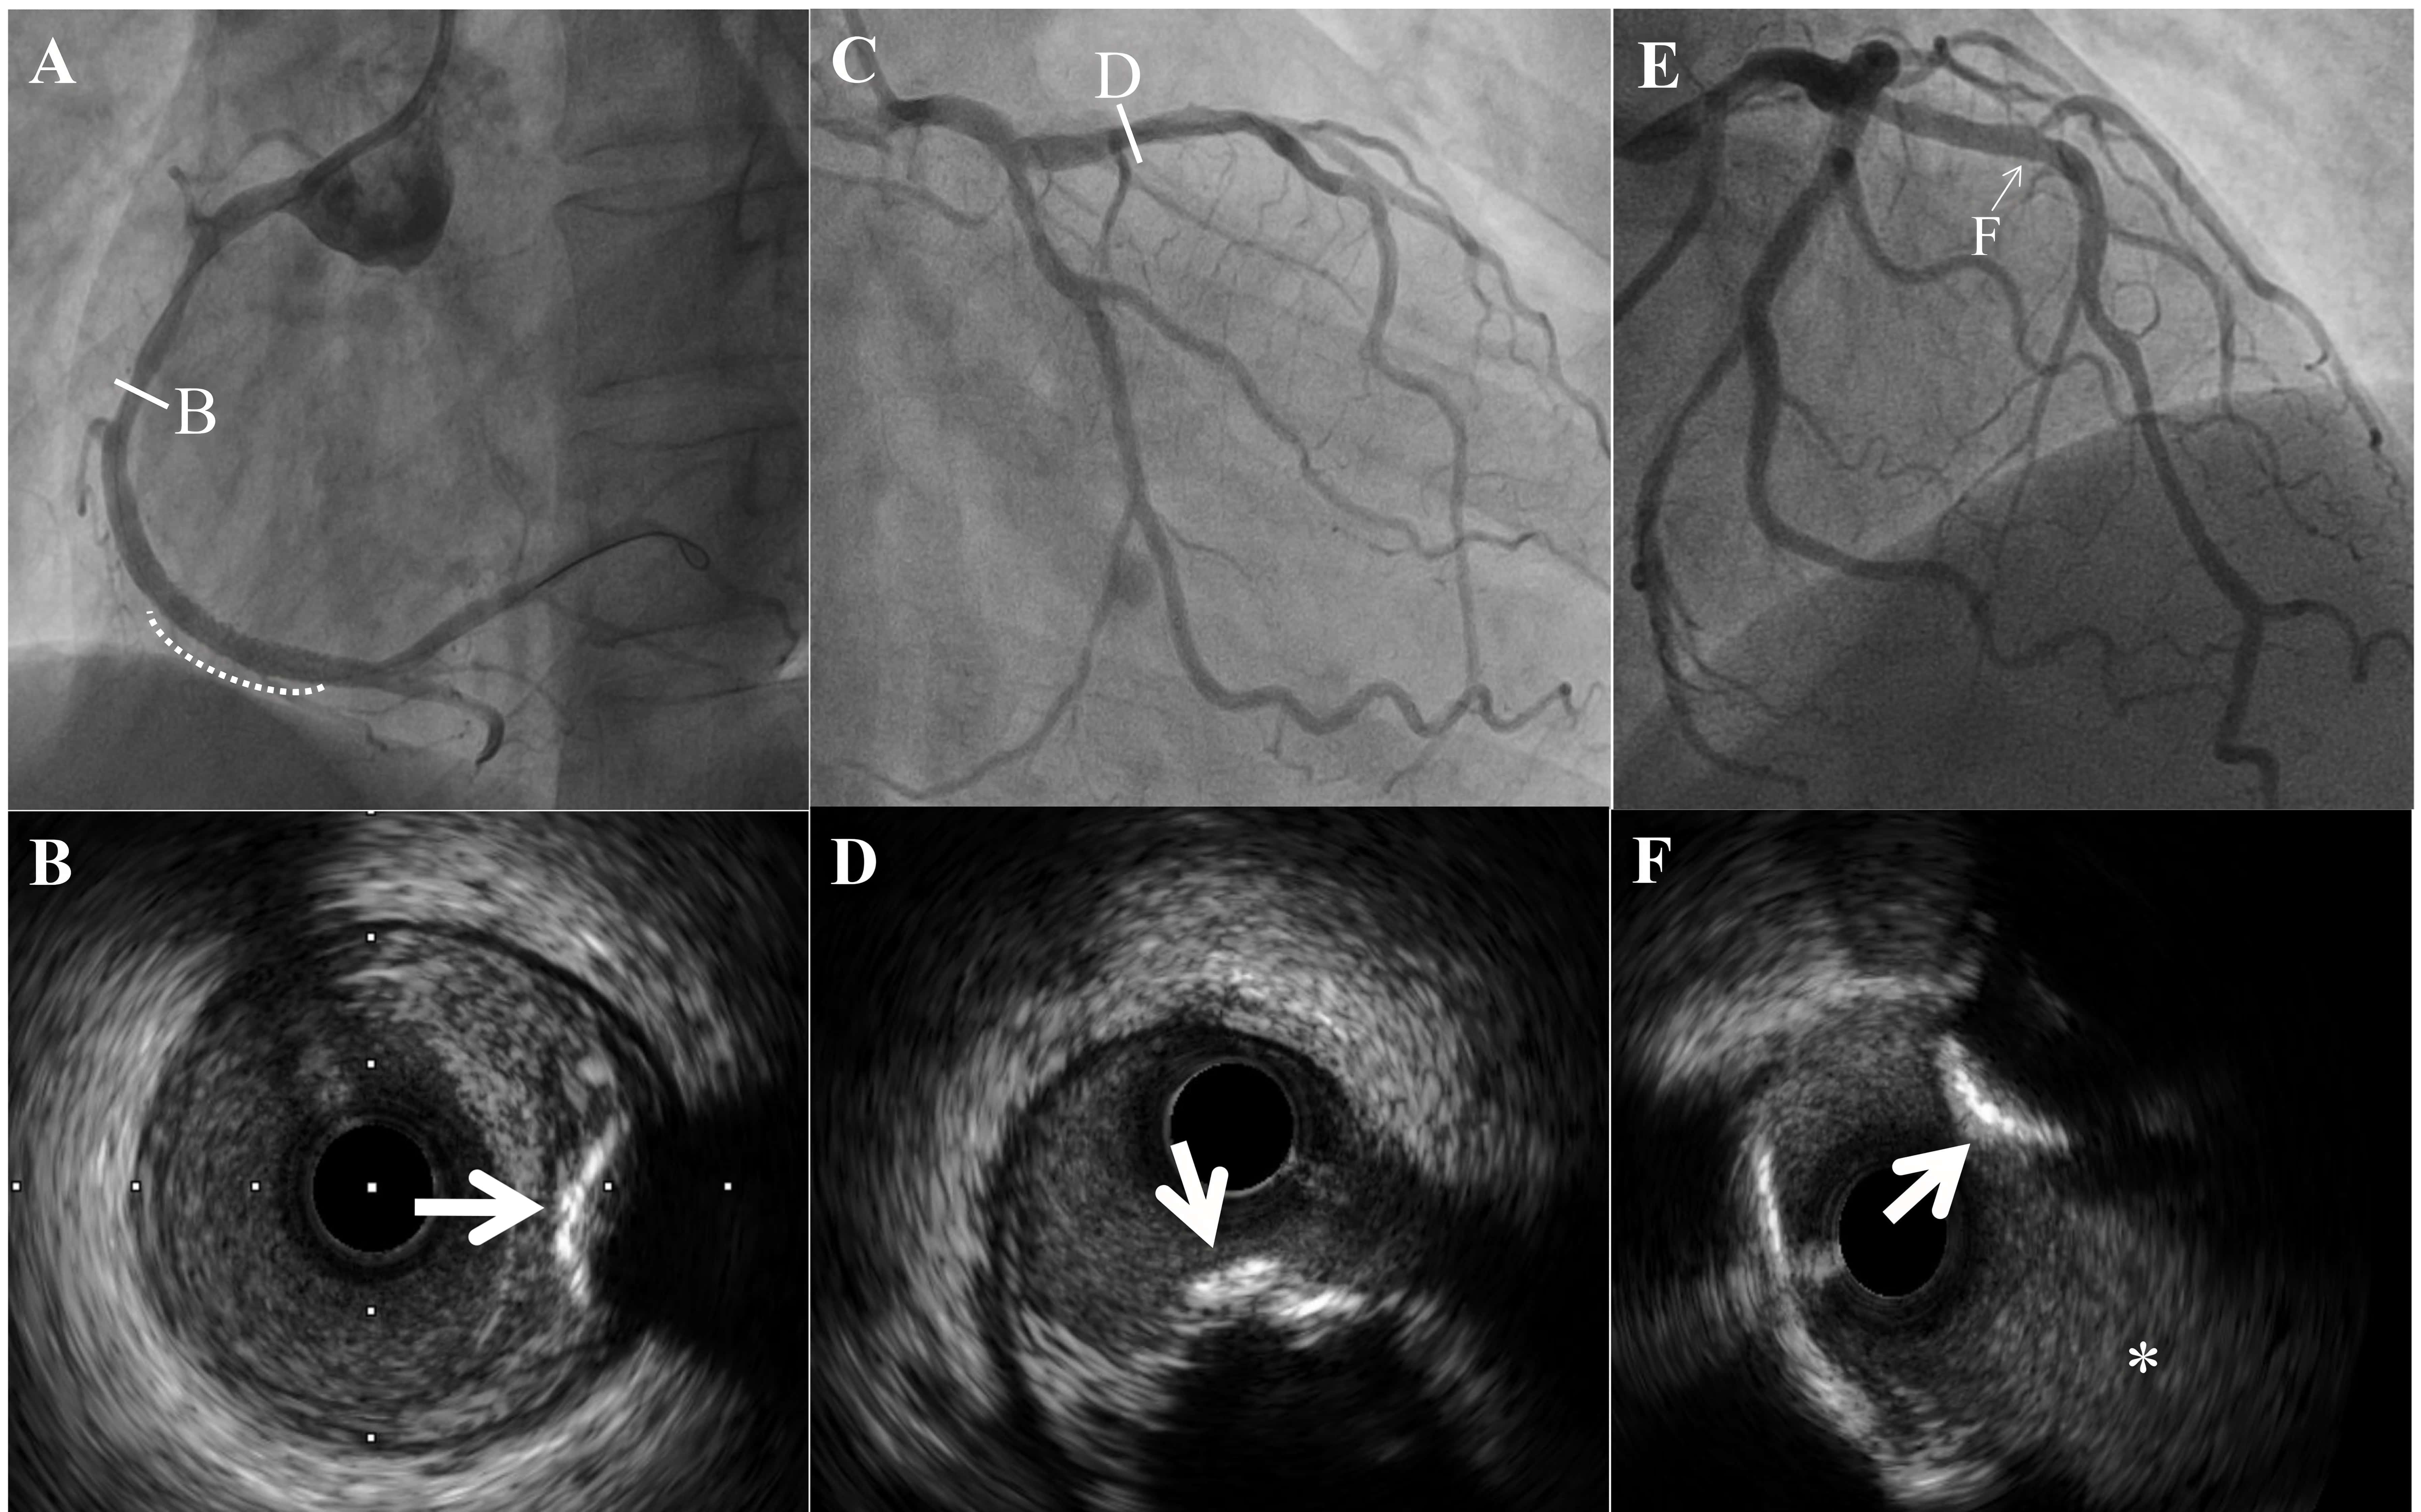

Fig. 2.Intravascular ultrasound images of a calcified nodule (CN). (A) White line indicate CN at the mid of right coronary artery. White dotted line indicate stent at culprit lesion. (B) Calcified nodule had a convex and irregular surface (white arrow), between intima and external elastic membrane. (C) White line indicate CN at the proximal of left anterior descending artery. (D) CN was superficial of the intima (white arrow). (E) White arrowhead indicate CN at the bifurcation site and the distal site of the branch. (F) CN was superficial of the intima (white arrow). White asterisk indicate the diagonal branch.